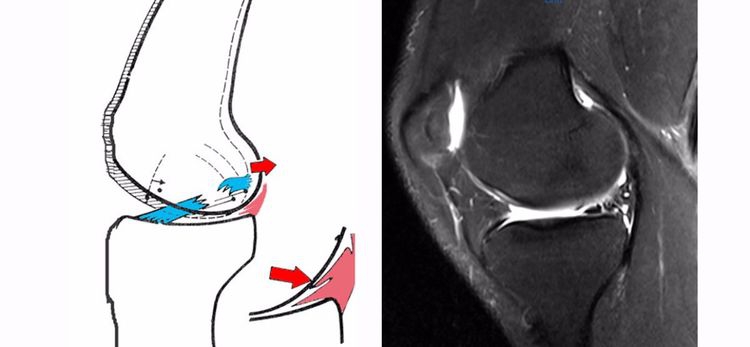

ACL损伤的间接征象:指ACL断裂后胫骨前移位出现的一系列改变。间接征象只能考虑可能有ACL损伤。

1.骨挫伤(轴移征):一旦ACL撕裂,胫骨就相对于股骨前移,使股骨外侧髁和胫骨外后方撞击,双方均出现水肿,而且膝关节屈曲的程度决定股骨髁挫伤的部位。

2.沟槽征:当股骨外髁骨因撞击造成的凹陷深度>2mm时称为沟槽征,代表受到撞击的暴力更大。

3.接吻征:膝关节过伸受伤时,胫骨前部撞击股骨髁前部,形成对称性骨挫伤;如果同时有一外翻力的话,膝关节外侧可出现对称性挫伤,这种对称性骨挫伤称为接吻征。也有人把轴移造成的股骨外侧髁和胫骨外后方水肿称为接吻征。

4.Segond骨折:胫骨平台前外侧撕脱骨折(胫骨平台腓骨尖上方,关节线下方的撕脱骨折),多因为下肢过度内翻加内旋暴力所致。骨折本身无特殊治疗。但其强烈提示ACL损伤(75–100%)。

5.前抽屉征:胫骨前移,外侧半月板后角裸露,由于MRI检查时病人为平卧位,胫骨应该因重力而后沉,因此前抽屉征往往暗示膝关节处于交锁状态。